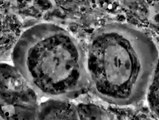

Meiosis I Drosophila spermatocyte

School

11 years ago

1:17